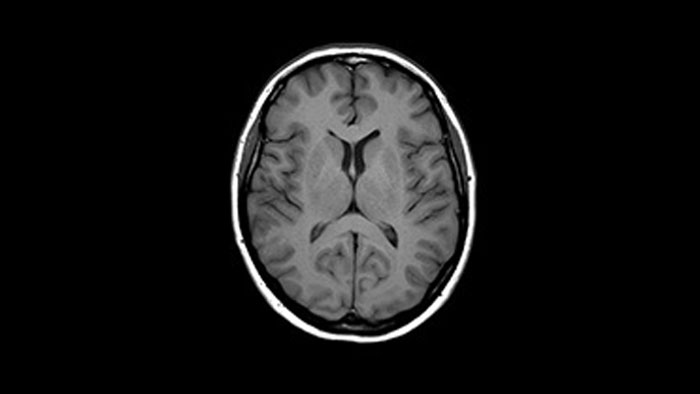

Compressed SENSE kann die meisten MR-Scansequenzen ohne Kompromisse bei der Bildqualität beschleunigen. Dadurch konnte die KOYASU Neurochirurgische Klinik (KNC) ihre Nutzungsdauer für MR-Untersuchungen verkürzen und den Durchsatz ihrer MR-Scanner um durchschnittlich drei zusätzliche Patienten pro Tag erhöhen.

Erfahren Sie mehr über die wichtigsten Prinzipien von Compressed SENSE und wie es einen Paradigmenwechsel in der Effizienz herbeiführt. Die Bildqualität ist ein Grundstein von Compressed SENSE; sie kann außerdem Scans beschleunigen, die räumliche Auflösung erhöhen und den Patientenkomfort in der klinischen Magnetresonanztomographie verbessern.

Das MR-Team am Kurashiki Zentralkrankenhaus nutzt Compressed SENSE in den meisten seiner Untersuchungsprotokolle für Gehirn, Wirbelsäule, Abdomen und Herz auf seinem Ingenia 1.5T. Patienten und Mitarbeiter begrüßen gleichermaßen die schnellen und hochwertigen MR-Scans.